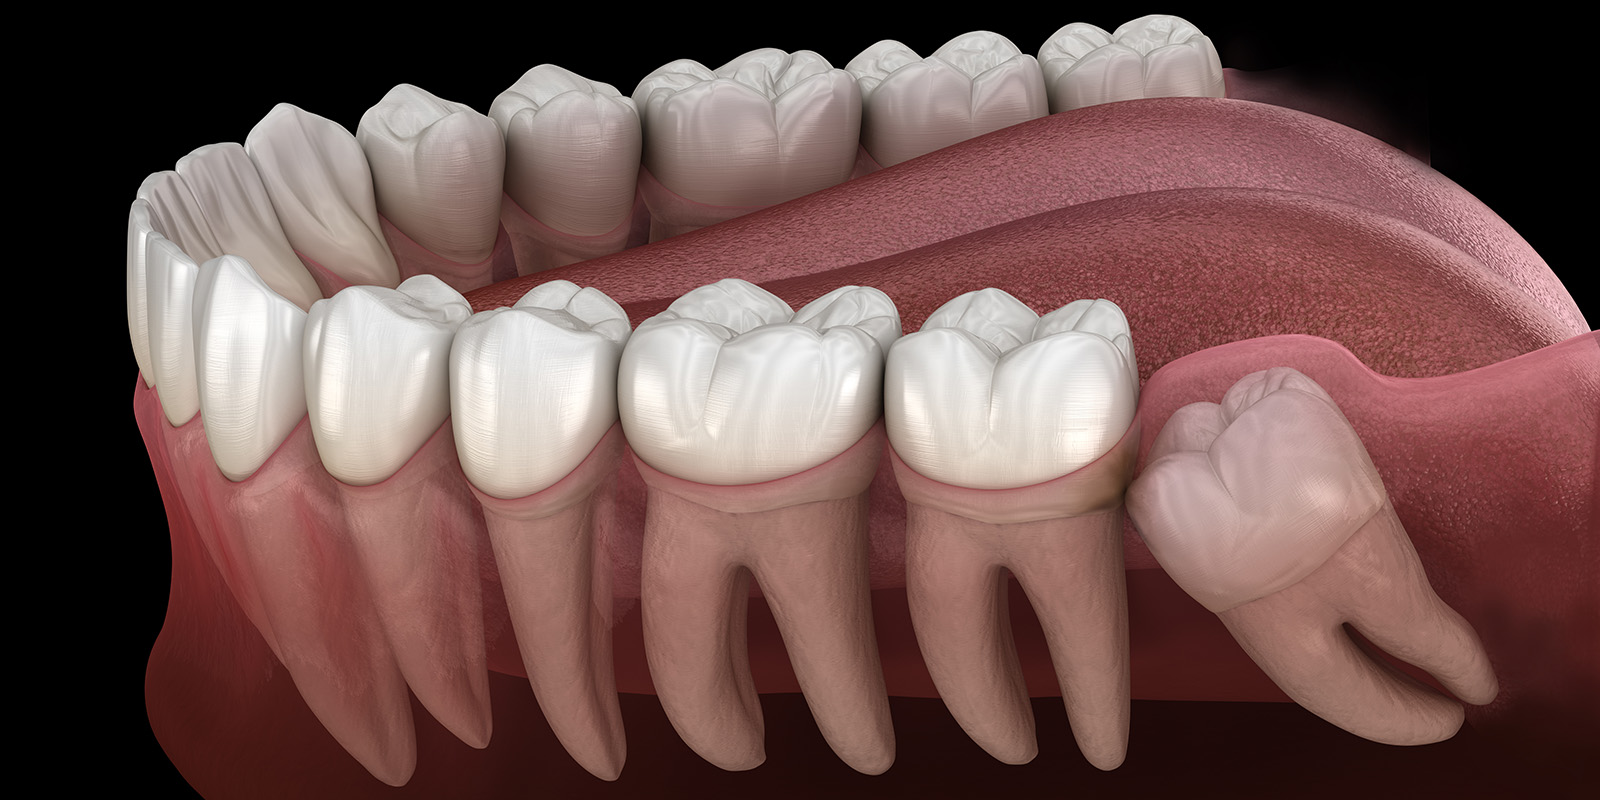

親知らずが生えそろっている下の歯のイラスト

親知らずは、第三大臼歯と呼ばれる8番目の歯になります。顎の大きさ、他の歯と同様に生えたり、横に生えたり、完全に埋まっていたり、元々なかったり、人によって全く違ってきます。

18歳から20歳くらいで生えてくる方が多いと思いますが、30歳を過ぎて生えてくる方も中にはいらっしゃいます。